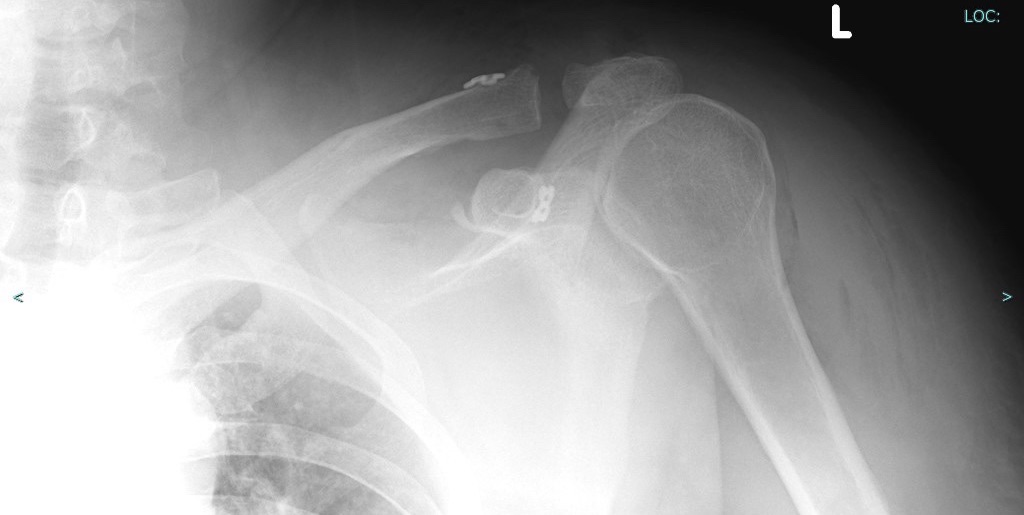

Après un traumatisme direct sur le moignon de l’épaule , une lésion sévère de l’articulation acromio claviculaire peut nécessiter une prise en charge chirurgicale.

Cette chirurgie peut se faire selon plusieurs modalités à « ciel ouvert » mais aussi sous arthroscopie, permettant des incisions plus petites et une récupération plus rapide .

Nous avons choisi cette dernière technique, moderne, pour prendre en charge ce patient.